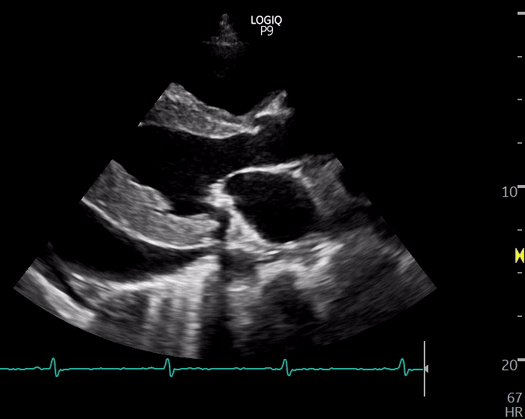

Abhilash Koratala, MDMedical College of Wisconsin Learning POCUS is like acquiring physical examination skills. It takes time and involves gaining proficiency in image acquisition, interpretation, and clinical integration. While hands-on practice is a vital component, the learner must…